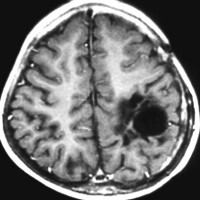

2歳の子どもの例

2歳の時に右の片麻痺と意識障害で発症しました。手術できれいにとれて,20年経ちますが再発はありませんし,運動麻痺もありません。この画像を見ると左の一次運動野が侵されていて,麻痺が治るということは信じられないのですが,2歳以下の小さな子どもの麻痺は治ることがあります。乳幼児のこの腫瘍は積極的な摘出を行った方がいいでしょう。